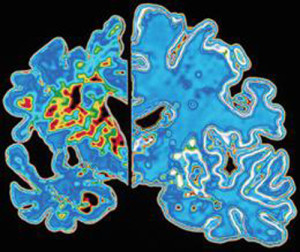

La proteina beta amiloide inizia il suo processo distruttivo aggregandosi in ammassi che alterano le comunicazioni tra le sinapsi nel...